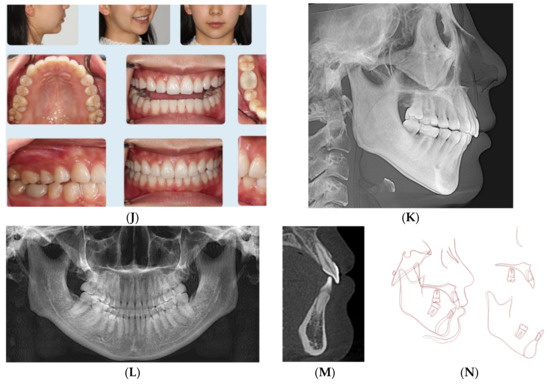

The patient was not interested in a fixed orthodontic appliance. Clinical records (Figure 4A–E) and Table 4 show the convex profile with recessive chin (ANB = 4.2°, SNB = 78.5°), left side occlusion was end-to -end and the right side was Class I with deep overbite (95%), with excessive curve of Spee and 3 mm overjet. She had no contributory medical or dental history to her current malocclusion.

Figure 4.

(A) Initial photographs showing convex profile with recessive chin and anterior crowding. (B) Initial digital models showing Class II Division 2 subdivision left side malocclusion with increased overbite and excessive curve of Spee. (C) CBCT-driven cephalometric radiograph showing convex profile with recessive chin and normally positioned upper incisors/nasolabial angle. (D) CBCT panoramic radiograph showing presence of all permanent teeth except lower third molar germs; no other noticeable intraoral bony lesion could be detected. (E) CBCT-driven sagittal screen of lower incisor showing increased overbite. (F) The digital treatment plan (ClinCheck) showing posterior teeth intrusion to help forward rotation of the mandible. (G) Upper arch digital treatment plan (ClinCheck) showing expansion and labial movement of the upper arch (blue—initial teeth position, white—final teeth position). (H) Lower arch digital treatment plan (ClinCheck) showing expansion (blue—initial teeth position, white — final teeth position) and lower anterior interproximal reduction to allow lower incisor intrusion and leveling /alignment of lower incisors. No attempt was made to procline the lower incisors. (I) Final photos showing improved patient’s profile and chin projection as well as aligned upper and lower incisors and Class I buccal occlusion both sides. Additionally, over bite has been improved compared to initial records. (J) CBCT-driven final cephalometric radiograph showing improved profile and chin projection. (K) Final CBCT-driven panoramic radiograph. (L) Final CBCT-driven sagittal screen radiograph of upper and lower incisors showing improved overbite and bone labial to both upper and lower incisors. (M) Superimposition of cephalometric tracing of before (black) and after (red) treatment showing improved forward chin projection, palatal movement of upper incisors roots while upper molars and incisors crowns moved forward by the dental decompensation, and profile and chin projection and lingual tipping of lower incisors.

Treatment plan and progress: The minimum overjet was challenging to allow the mandible to be projected forward, so dental decompensation protocol was applied to this patient. In other words, treatment planning included advancing the upper arch forward using class III elastics (3/16-4.5 ounces full time) as well as expanding the upper arch at the same time in addition to intruding posterior teeth as moving the upper arch forward. Another challenge in this case was the excessive curve of Spee with moderate lower incisor crowding (6 mm). So in order to advance the lower arch, the excessive curve of Spee should be leveled, also due to the high angle presentation of this case (FMA = 30.4° Table 4). Another challenge in the lower arch was the lower incisor inclination (L1 MP = 84.9o). Hence, the initial goal was to move lower incisors slightly lingually to minimize anterior interference once the mandible is rotated forward or at least maintaining their original position. In addition, the retroclined upper incisors (U1-SN = 100.6o) would allow forward positioning/proclination of upper incisors. Treatment planning also included utilization of Class III elastic button cutouts to the upper first molars palatally to assist with upper arch expansion as well as lower first premolars (3/16-4.5 ounces) full time. She was provided with a VPro5 appliance and directed to use it for 5 minutes every day. Additionally, the patient was provided with vertical-pull chin cup (Jaw Bra, Chanhassen, MN USA) to use every night. She was able to change her aligners every 4–5 days.

Her treatment involved 23 aligners, and no additional aligners were needed afterwards. Treatment time was 4 months. Then she was given 4 sets of Vivera retainers. Final records were taken at one year from the original records that show better chin-forward projection (Figure 4I–M) (Table 4). Superimposition of before and final CBCT-driven cephalometric radiographs show the forward projection of the chin and the decompensated upper and lower incisors.